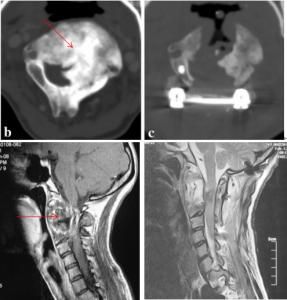

此外CT掃描、MRI檢查均顯示出其特有的徵象。

成年人出現顱內壓增高及小腦體徵即應為考慮血管網狀細胞瘤的可能。如發現有視網膜血管網狀細胞瘤,胰腺或腎臟等內臟的先天性多發性囊腫,或血管瘤、紅細胞增多症,或有家族史者,更應考慮為本病。CT掃描等必要輔助檢查有助診斷及定位。